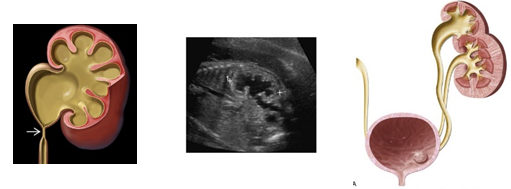

C. Invisible kidney

: 다음의 그림과 같이 sagittal view에서 renal fossa가 비어 있어 adrenal gland의 위치와 모양이 바뀌어 lying-down appearance를 관찰할 수 있습니다. 그 외 반대편 kidney는 hypertrophy해 보이며, coronal view에서 renal artery가 한 쪽이 없음을 같이 관찰할 수 있습니다.